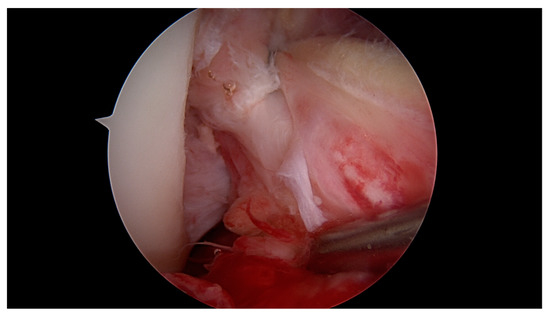

Primary Proximal ACL Repair: A Biomechanical Evaluation of Different Arthroscopic Suture Configurations

by Steffen B. Rosslenbroich, Andrea Achtnich, Cathrin Brodkorb, Clemens Kösters, Carolin Kreis, Sebastian Metzlaff, Benedikt Schliemann and Wolf Petersen

J. Clin. Med. 2023, 12(6), 2340; https://doi.org/10.3390/jcm12062340 - 17 Mar 2023

Purpose: Several suture techniques have been described in the past for direct ACL repair with poor healing capacity and a high re-rupture rate. Therefore, we investigated a refixation technique for acute primary proximal ACL repair. The purpose of this study is to [...] Read more.

Purpose: Several suture techniques have been described in the past for direct ACL repair with poor healing capacity and a high re-rupture rate. Therefore, we investigated a refixation technique for acute primary proximal ACL repair. The purpose of this study is to compare the biomechanical properties of different suture configurations using a knotless anchor. Methods: In this study, 35 fresh-frozen porcine knees underwent proximal ACL refixation. First, in 10 porcine femora, the biomechanical properties of the knotless anchor, without the ligament attached, were tested. Then, three different suture configurations were evaluated to reattach the remaining ACL. Using a material testing machine, the structural properties were evaluated for cyclic loading followed by loading to failure. Results: The ultimate failure load of the knotless anchor was 198, 76 N ± 23, 4 N significantly higher than all of the tested ACL suture configurations. Comparing the different configurations, the modified Kessler–Bunnell suture showed significant superior ultimate failure load, with 81, 2 N ± 15, 6 N compared to the twofold and single sutures (50, 5 N ± 14 N and 37, 5 ± 3, 8 N). In cyclic loading, there was no significant difference noted for the different configurations in terms of stiffness and elongation. Conclusions: The results of this in vitro study show that when performing ACL suture using a knotless anchor, a modified Kessler–Bunnell suture provides superior biomechanical properties than a single and a twofold suture. Within this construct, no failure at the bone–anchor interface was seen. Clinical relevance: Since primary suture repair techniques of ACL tears have been abandoned because of inconsistent results, ACL reconstruction remains the gold standard of treating ACL tears. However, with the latest improvements in surgical techniques, instrumentation, hardware and imaging, primary ACL suture repair might be a treatment option for a select group of patients. By establishing an arthroscopic technique in which proximal ACL avulsion can be reattached, the original ACL can be preserved by using a knotless anchor and a threefold suture configuration. Nevertheless, this technique provides an inferior ultimate failure load compared to graft techniques, so a careful rehabilitation program must be followed if using this technique in vivo. Full article

Show Figures

Figure 1